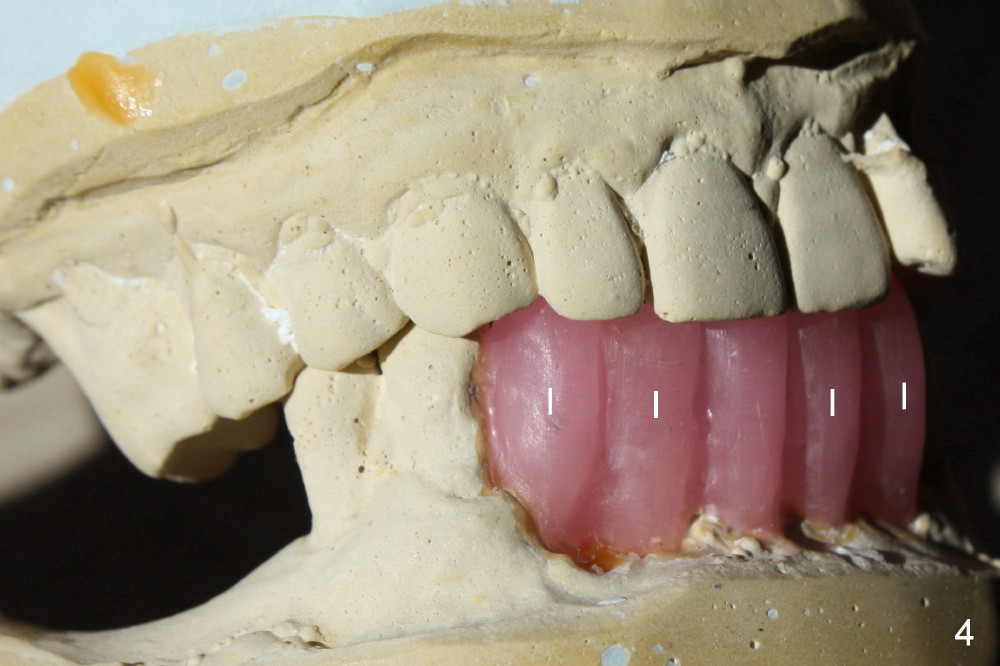

A 52-year-old man seeks treatment 2 months following loss of #22-27 fixed partial denture (FPD) (Fig.1,2). The remaining dentition has moderate to severe chronic periodontitis. Scaling & root planing has been done for the upper arch. Full mouth reconstruction is planned for the lower one in two steps. In the first procedure, the teeth #18, 20 and 21 are extracted; an incision is made from #20 to #27; two immediate implants are placed at the sites of #20,21 (one or two piece, Fig.3,5 X); another two implants at #22,27 (recently healed sites: Fig.3-5: I) and two one piece implants at lateral incisor region (I: for an implant supported FPD). In case one of the lower left premolars cannot have an implant due to proximity to the nerve, a FPD can be fabricated in the canine/premolar sextant. A splinted immediate provisional restoration will be fabricated from #20-27 immediately.